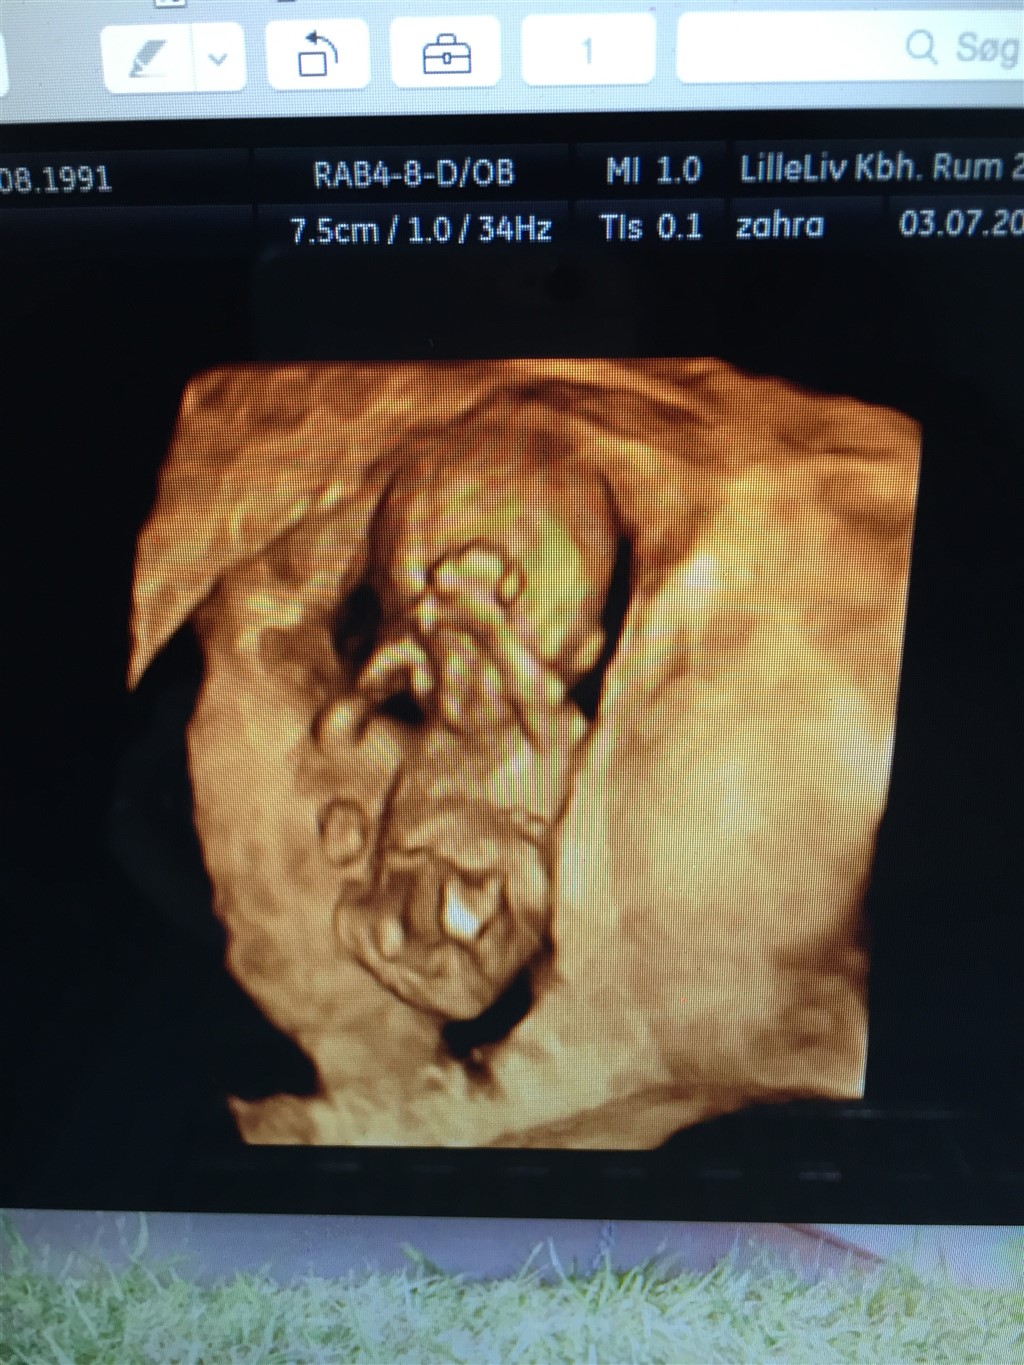

Vi har ikke været til nf skanning endnu så det var egentlig bare for sjov fordi vi selv var lidt uenige. Men kan da lige sætte et billede ind her

Vedhæftede fotos (klik for at se i fuld størrelse)